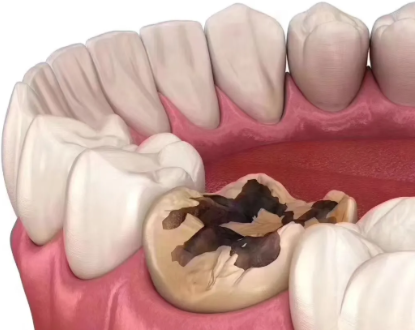

龋齿对牙齿结构的破坏是一个渐进的过程。一开始,可能只是牙齿表面出现一些小问题,比如牙齿上出现小黑点或者小斑块,这就是浅龋的表现。浅龋的时候,特别多人可能并没有明显的感觉,所以容易被忽视。但如果不及时处理,浅龋就会逐渐发展为中龋。

中龋阶段,细菌已经深入到牙齿的本质层了。这时候,牙齿可能会对冷热酸甜等刺激有一些敏感反应,吃冷热食物或者甜食的时候会觉得牙齿有点不舒服。而且,牙齿上可能会出现一些小窟窿,这些窟窿就像是一个个“陷阱”,容易藏污纳垢,让细菌更容易滋生。

如果中龋还是没有得到治疗,就会进一步发展为深龋。深龋意味着细菌已经接近或者到达了牙髓腔。这时候,牙齿上的窟窿会变得更大更深,牙齿的结构受到了重度的破坏。牙齿的坚固性大大降低,可能稍微咬一下硬一点的东西,牙齿就会出现裂纹甚至折断。